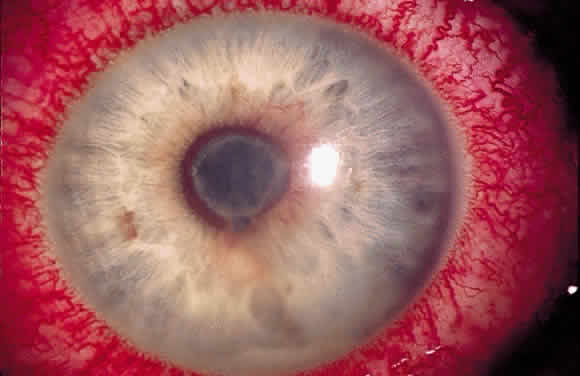

Long-standing chronic iridocyclitis, especially in children, may result in calcific band keratopathy, the deposition of calcium hydroxyapatite in the cornea at the level of Bowman's membrane. Band keratopathy usually begins as grayish-white opacities at the periphery of the interpalpebral region. The opacification may spread centrally and in time may form a complete band within the interpalpebral zone. A lucid interval is noted between the band and the limbus because Bowman's layer does not extend to the absolute limbus.6 Small clear areas are noted in the opacity, representing the location where corneal nerves penetrate Bowman's layer. These holes impart a “Swiss cheese” appearance to band keratopathy (Fig. 1). Band keratopathy should be distinguished from Vogt's limbal girdle and spheroidal degeneration. Occasionally, band keratopathy is atypical and starts centrally. Rarely, it forms a reticular pattern resembling lattice dystrophy called superficial reticular degeneration of Koby.7